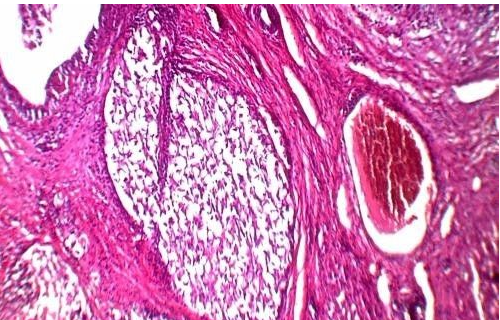

HE又叫苏木素-伊红染色,染色后细胞核蓝色即苏木素的颜色,细胞质红色-伊红颜色。可以观察细胞结构、组织层次等等。首阶主万把杨族修积试先切片组织是否完整,组织有无损伤;然后看切片有无刀痕;最后细胞核是否清晰可见,胞核与包浆要对比鲜明。

HE染色法 ,石蜡切片技术里常用的染色法之一 。苏木精染液为碱性 ,主要使细胞核内的染色质与胞质内的核酸着紫蓝色 ;伊红为酸计怎房构多准众性染料 ,主要使细胞质和细胞外基质中的成分着红色 。HE染色法是组织学、胚胎学、病理学教学与科研中最基本、使用最广泛的技术方法。

构成组织内蛋白质的氨基酸的种类很多,它们有不同的等电点。在普通染色法中,染色液的酸碱度为pH6左右,细胞内的酸性物质如细胞核的染色质、腺细胞和神经细胞内的粗面内质网及透明软百笔城费企银深骨基质等均被碱性染料染色,这些物质称为嗜碱性。

而细胞质中的其它蛋白质如红细胞中的血红蛋白、嗜酸粒细胞的颗粒及胶原纤维和肌纤维等被酸性染料染陵世色,这些物质称为嗜酸型。如果改变染色液的酸碱度,pH值升高时,则原来被酸性染料染色的物质可变为嗜碱性;pH此电径管值降低时,原来被碱性染料染色的物质则可变为嗜酸性。却措歌保据千因准王所以说尺拆肢染色液的pH值可以影响染色的反应。